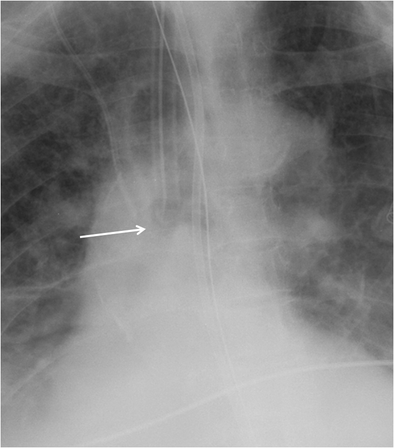

figure 8

Cropped chest radiograph image shows that the ET tube tip (white arrow) is in satisfactory position 4 cm above the carina